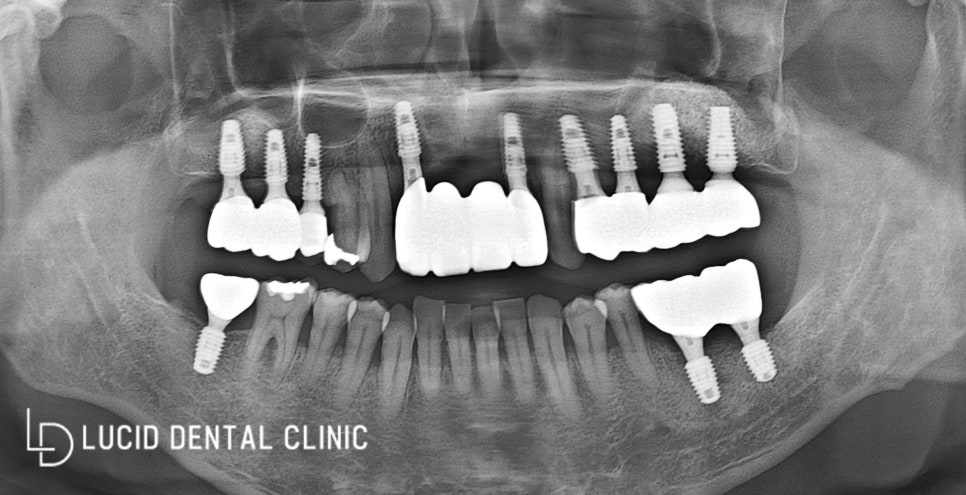

자 이제 우리 논현동 치과에서

치아 상태가 안 좋았던 것들에 대한

모든 진료 계획을 실행해서

완성한 파노라마 x-ray 사진이에요.

진단하기 전 파노라마 x-ray와 달리

현재 구강 내 모든 면이 골고루

사용할 수 있게 완성이 됐습니다.

엑스레이로 확인해 보니,

단단하게 식립이 잘 되었고

성공적으로 치료되었네요 :)